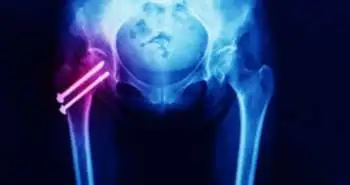

Percutaneous transiliac–transsacral screw fixation of sacral fragility fractures improved pain, ambulation, and the rate of disposition to home without increasing complications or length of stay.

J. Brock Walker and colleagues explained the role of percutaneous transiliac-transsacral screw fixation in improving sacral fragility fractures related ambulation, pain, length of stay and disposition rate to home. This technique became popular in mid and late 1990 to fix posterior pelvic ring injuries. Nowadays, it is used to manage issues with sacral fractures.

A total of 41 older patients who suffered from sacral fractures from August 2015 to August 2017 were selected retrospectively. Out of these, 25 treated non-operatively and 16 treated with percutaneous transiliac-transsacral screw fixation. The ambulation, length of stay, pain and disposition rate to home were measured as significant outcomes of the analysis.

The operational group showed improved pain (3.9 points) measured by VAS as compared to non-operative group( 0.6 points, p<0.001). Hundred per cent of operational group patients were able to ambulate as compared to 72% patients of the non-operational group (p=0.03). The operational group also exhibited higher ( 95 ft vs 35 ft) average distance ambulating during discharge. Both groups presented an almost equal length of stay (operative – 3.6 days; non-operative – 4.2 days). A total of 75% patients from operational group discharged to home as compared to 20% from non-operational group. No complications were noticed during operation. Overall, the percutaneous transiliac-transsacral screw fixation able to improves sacral fragility fractures related problems. However, more research is required to assess technique advantages in regards to medium and long-term outcomes.